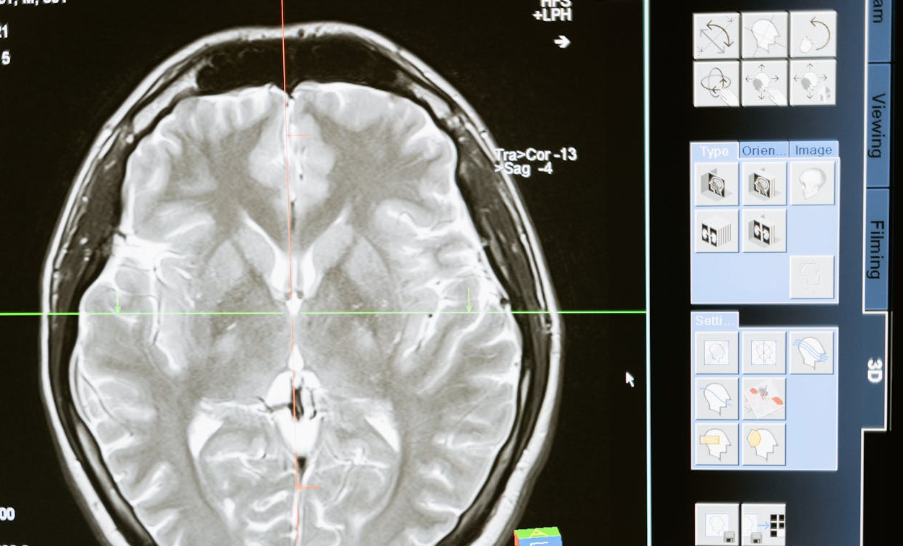

AI-powered systems analyze medical imaging, blood tests, and patient history to identify patterns that human eyes might miss. Early-stage cancers, cardiovascular risks, and neurological disorders can now be detected faster and more accurately.